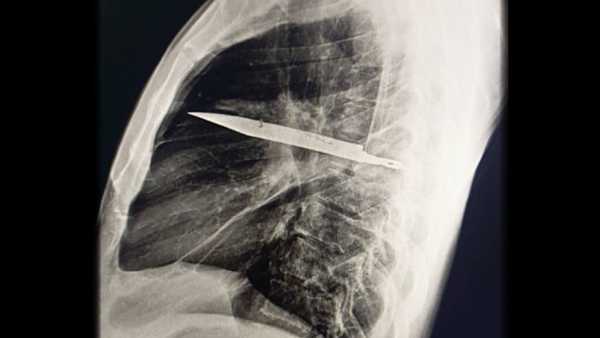

Ніж зламався в грудях чоловіка, і він не помічав цього 8 років